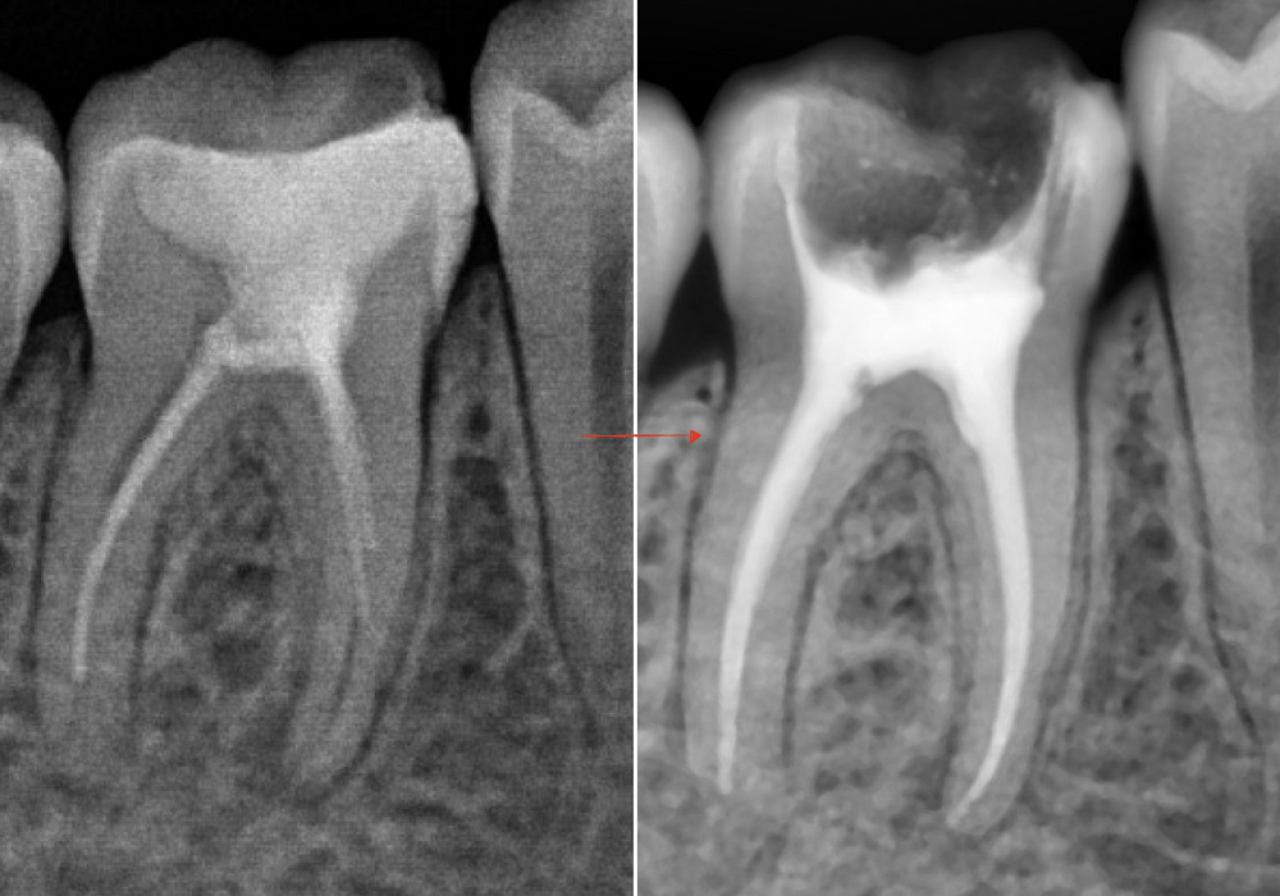

Endodoncija - liječenje zubne pulpe

Kada uznapredovali karijes ili trauma dovedu do upale zubnog živca, to može rezultirati jakoj boli u zubu. Endodontski zahvat uključuje pažljivo uklanjanje upaljenog živca te punjenje korijenskog kanala bioinertnom, homogenom masom. Da bi terapija bila dugoročno uspješna, često koristimo dentalni mikroskop i specifične materijale kako bismo sačuvali zub.

U sklopu konzervativne dentalne medicine, nudimo i ugradnju bijelih kompozitnih i keramičkih(inlay i onlay) plombi.